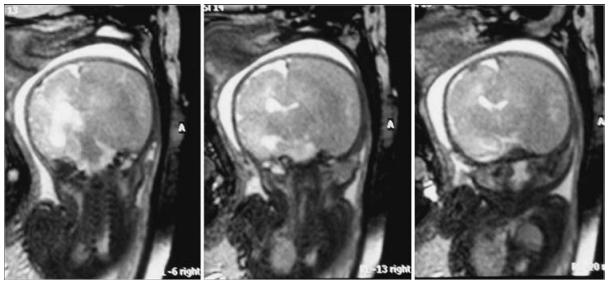

在创伤10天后前往医院进行产前MR影像学评估,发现右侧脑血肿(硬脑膜下血肿)较大,压迫同侧脑室,导致中线移位;且左侧脑室稍大(12.5 mm,图1)。34周时进行检查,脑室肿大增加(9 × 17 mm)。此时距离预产期仅剩几周,但由于颅内外出血,情况十分危险,必须接受剖腹产手术。

图1:孕31周胎儿MR图像显示,右侧大脑半球有一个巨大的颅内脑血肿移位。右侧脑室向对侧移位,左侧脑室轻度增大。